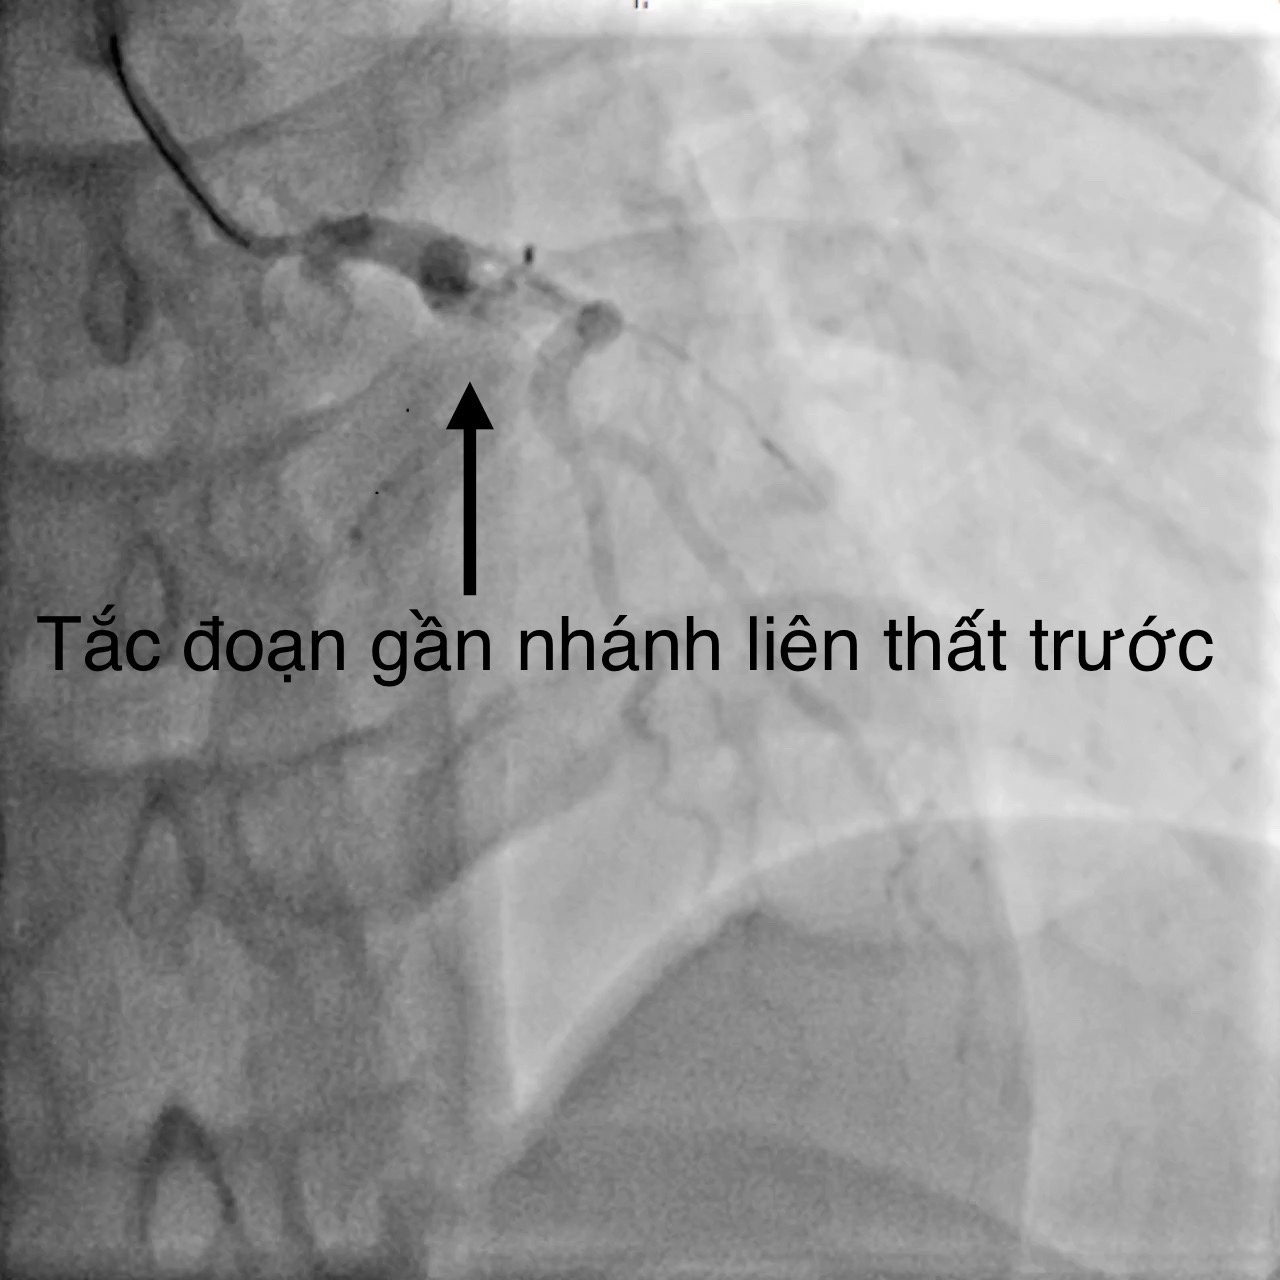

Bệnh nhân đã được hội chẩn nhiều chuyên khoa: Tim mạch can thiệp, Nội Tim mạch, Ngoại Lồng mạch máu, Ngoại thần kinh, Mắt... Bệnh nhân có chỉ định can thiệp mạch vành cấp cứu do BSCKII. Trần Văn Triệu – Phó khoa phụ trách khoa Tim mạch can thiệp thực hiện, kết quả ghi nhận tắc từ lỗ động mạch vành liên thất trước (động mạch vành trái), tổn thương dạng bóc tách. Can thiệp thành công bằng một stent phủ thuốc với thời gian 35 phút. Chụp kiểm tra dòng chảy tốt , được chuyển khoa Tim mạch can thiệp chăm sóc và điều trị.